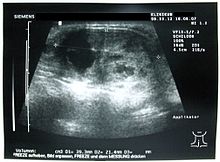

Ultraschalluntersuchung der Schilddrüse – hier ein großer Schilddrüsenknoten

Die Schilddrüse kann beim Menschen durch Abtasten (Palpation) des Halses untersucht werden. Bei Hunden gilt eine tastbare Schilddrüse bereits als vergrößert. Eine ausgeprägte Struma ist beim Menschen sichtbar. Eine orientierende Untersuchung der Schilddrüse sollte im Prinzip von jedem Arzt vorgenommen werden können, da Schilddrüsenerkrankungen beim Menschen sehr häufig sind und Berührungspunkte mit fast allen Teilgebieten der Medizin bestehen. Besondere Erfahrung auf diesem Gebiet haben in der Regel Endokrinologen und Nuklearmediziner.

In der bildgebenden Diagnostik werden hauptsächlich der Ultraschall und zur weiteren Abklärung bei Knoten und Funktionsstörungen die Szintigrafie eingesetzt, für spezielle Fragestellungen auch die Computertomografie und Kernspintomografie.